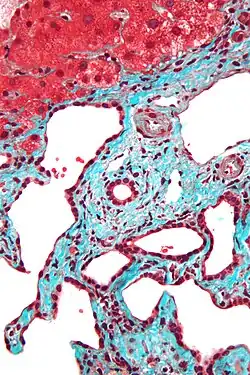

Histopathology of a bile duct hamartoma, high magnification, H&E stain. It shows typical features of bile duct hamartoma: Small to medium sized, irregularly shaped bile ducts lined by bland cuboidal epithelium (may also be flattened). Prominent intervening collagenous stroma. Bile ducts containing eosinophilic debris (may also contain inspissated bile) -

Low magnification micrograph of a bile duct hamartoma. Trichrome stain. -